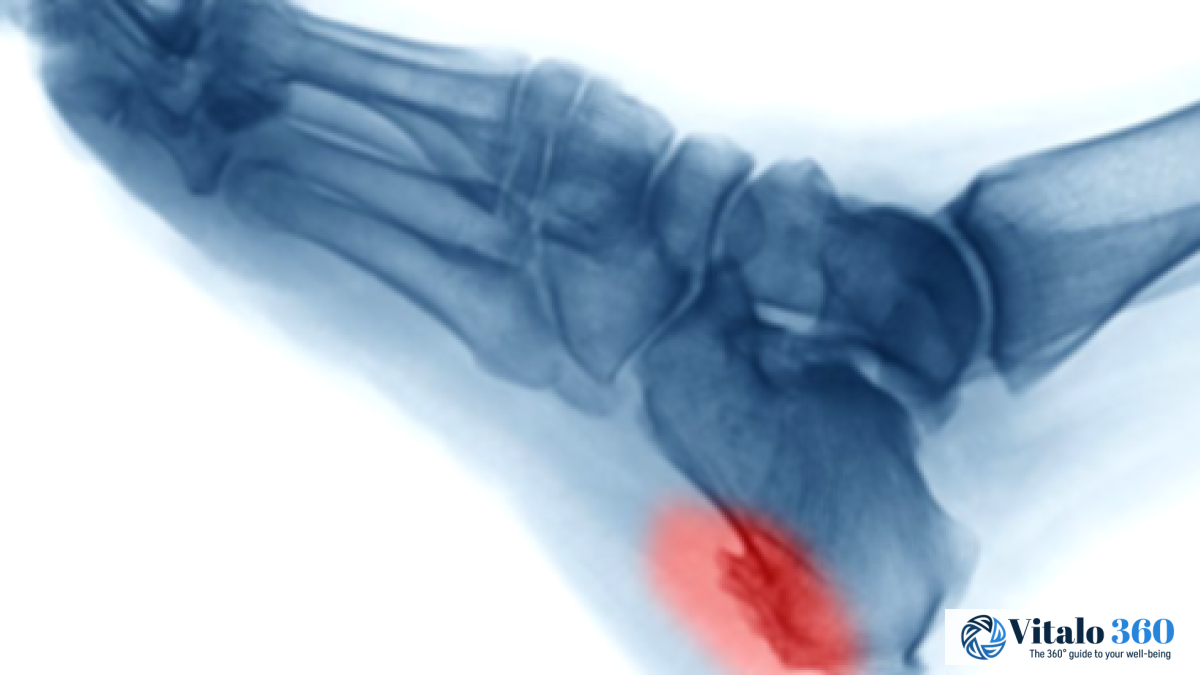

Heel spurs are bony growths on the heel that can cause foot pain; find out about their symptoms, causes such as strain or unsupportive shoes, risk factors, and various treatments like rest, ice, or shoe inserts.